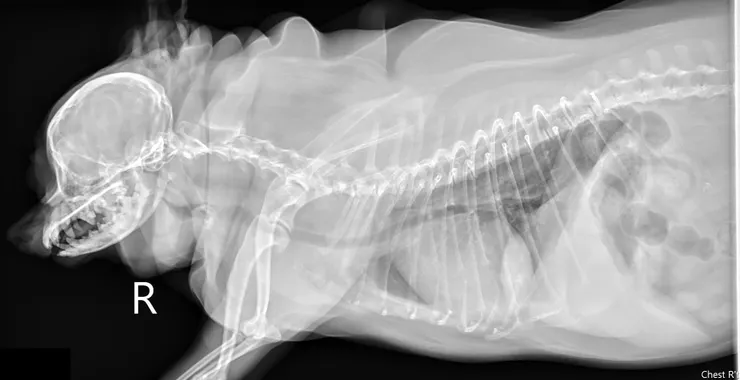

就診原因是這1-2週呼吸越來越不順,這幾天睡著就會無法呼吸

想要安排電腦斷層檢查排除鼻道到咽喉部腫瘤造成阻塞的可能並安排軟顎修整手術

在等待期間因為擔心睡眠呼吸中止越來越嚴重所以提早住院

住院期間只要睡著就會呼吸暫停且低血氧,需要有人在旁邊不停地把她叫醒

所以我們的故事主角胖胖後來怎麼樣了呢?

胖胖後來做了軟顎修整手術後,住氧氣房住了2-3週,期間嚴格執行減重計畫,在一個月後體重來到5.5公斤左右,症狀也漸漸改善了,終於可以比較正常的生活囉!